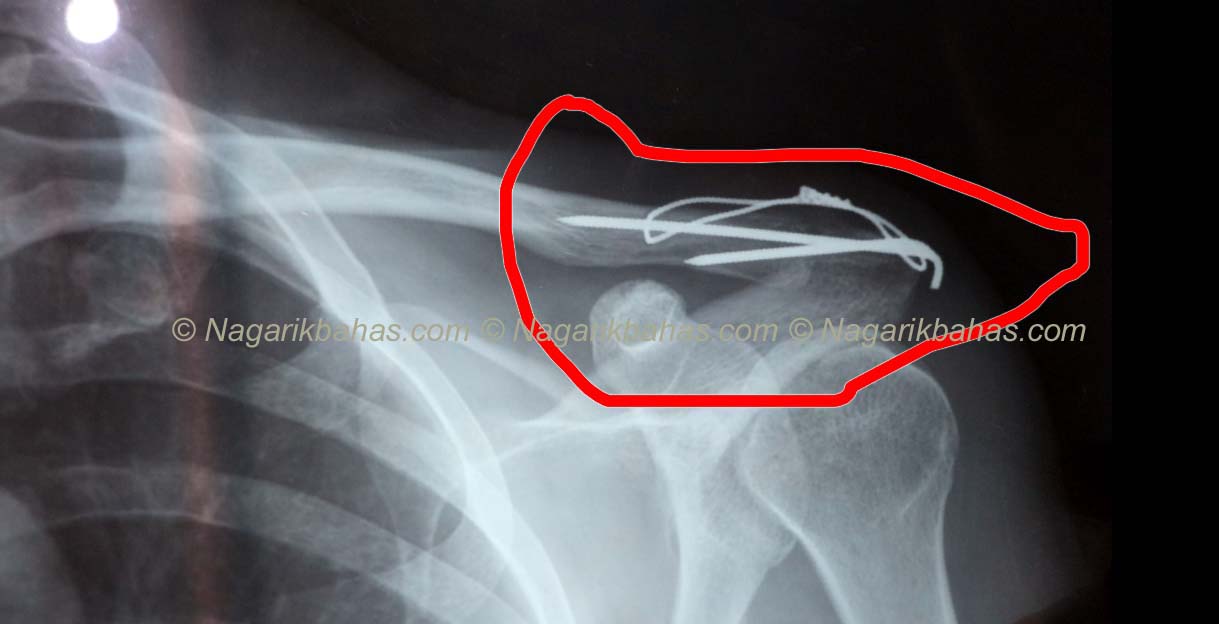

जाँचको क्रममा काठमाडौं र गाईघाटको दुबै अस्पतालले हड्डी जोडिदै गएको राम्रो भएको रिपोर्ट दिएको थियो । आफ्न्तको सल्लाह अनुसार २०७६ कातिक ७ गते गाईघाट सिभिल हस्पिटलमा स्टिल निकाल्ने काम भयो । अप्रेशन गरेर स्टिल झिके छ भन्दै ढुक्क थिए जव घर पुगेपछि दुःख्न नछोडेपछि पुनः नेपाल अर्थोपेडिक अस्पतला काठमाडौंमा एक्सरे गर्दा पो स्टिल निकाल्नु पर्नेमा मेरो कुमको हड्डी नै निकालेर फ्याकेको रहस्य पत्ता लाग्यो ।

अर्थोपेडिकका डाक्टरले हड्डी नै निकालेर फ्याकेको बताएपछि आफु छागाबाट झरेझै भए, “पत्रकार सम्मेलनमा रिपोर्ट देखाउदै खत्रीले भने “अस्पताल र डाक्टरले नियतबस मेरो हड्डी काटेर धेरै खर्च गराउन खोजेको भन्ने पनि लागेको छ ।” राम्रो रिपोर्टको आधारमा स्टिल निकाल्नु पर्ने अवस्थामा काठमाडौं नै जान खोजेका विरामीलाई यहि ठीक हुन्छ भन्दै जबरजस्ती अप्रेशन गर्दा गाईघाट सिभिल अस्पतालका डाक्टरको लापरवाही गरेको पिडित खत्रीले बताए ।